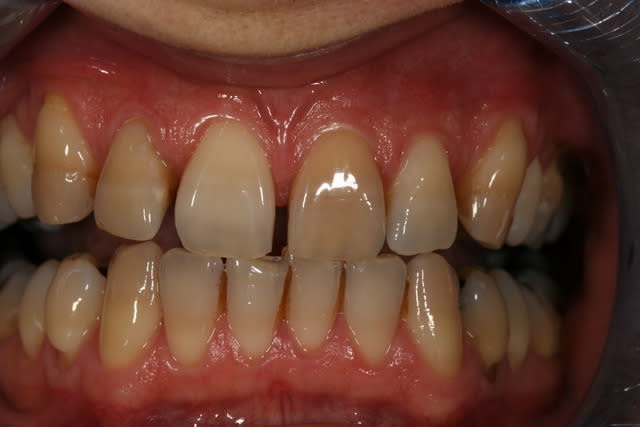

Un cas de blanchiment interne .

Cas simple et pourtant ... j'ai été obligé de prendre un risque . Lequel ?

Indice : on lui avait proposé la dévit et une céram .

C'est un blanchiment unitaire sur dent vivante ayant eu traumatisme.

C'est un blanchiment interne comme si l'endo était faite (après recherche effrénée d'un hypothétique canal), et après contrôle +++ d'une isolation +++ . La patiente n'a aucun souvenir d'un traumatisme sur cette dent .